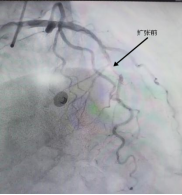

一位中年男性,因“胸闷气促”入院,此次发病后冠脉造影提示前降支中远段狭窄80%。心内科团队经过精准评估后发现,患者血管直径只有2.5mm,没有植入新支架,而是用药物球囊扩张成形术解决问题。手术成功打通狭窄血管,实现血运重建,患者体内未增加任何金属异物,有效缓解了患者病痛。